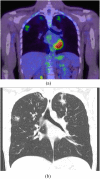

The objectives of this article were: (1) to review common and rare manifestations of systemic and pulmonary Langerhans cell histiocytosis, Rosai-Dorfman disease, Erdheim-Chester disease and juvenile xanthogranuloma; (2) to provide the reader with important pathologic, epidemiologic and clinical features of these diseases. The histiocytoses are a diverse group of diseases which typically manifest with multiorgan involvement. Understanding the pathologic, epidemiologic and clinical features of these entities can help the radiologist suggest an accurate diagnosis of histiocytosis when typical imaging features are encountered.